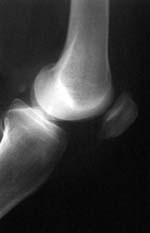

Los Rayos-X, descubiertos a finales del siglo 18 por el físico alemán Wilhelm Röntgen, se emplean

fundamentalmente para obtener radiografías de apoyo al diagnóstico médico, así como en investigaciones metalúrgicas, científicas y

en el análisis de obras de arte.

Radiografía obtenida por Rayos-X.